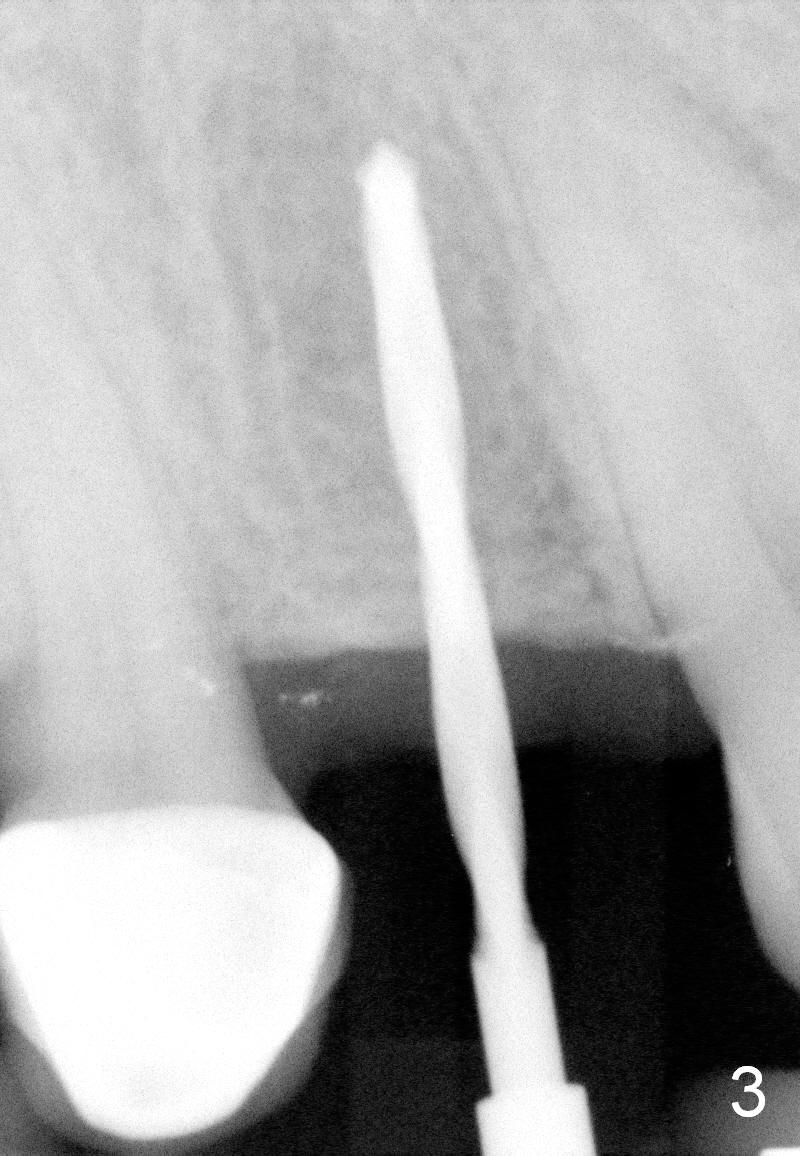

A 66-year-old man has lost several teeth (Fig.1,2). There is a particularly wide mesiodistal space for the site of #5 (Fig.1), probably due to distalization of the tooth #4 under heavy occlusion (Fig.2 arrow). A 4 mm tissue punch is used for access, followed by 1.6 mm pilot drill (Fig.3). After trajectory adjustment, a 2 mm parallel pin is inserted (Fig.4); later the osteotomy is moved distally (arrow). Finally a 4.5x14 mm implant is placed (Fig.5 I). Due to limited access, the implant is placed a little deeper than necessary; the gingival cuff of an abutment has to be longer (Fig.6 A: 5.8x4(3) mm). An immediate provisional is fabricated (Fig.7,8 P). The provisional looks wide (Fig.7). When the implant osteointegrates, limited orthodontic treatment will be done to idealize the space of #5 as follows.